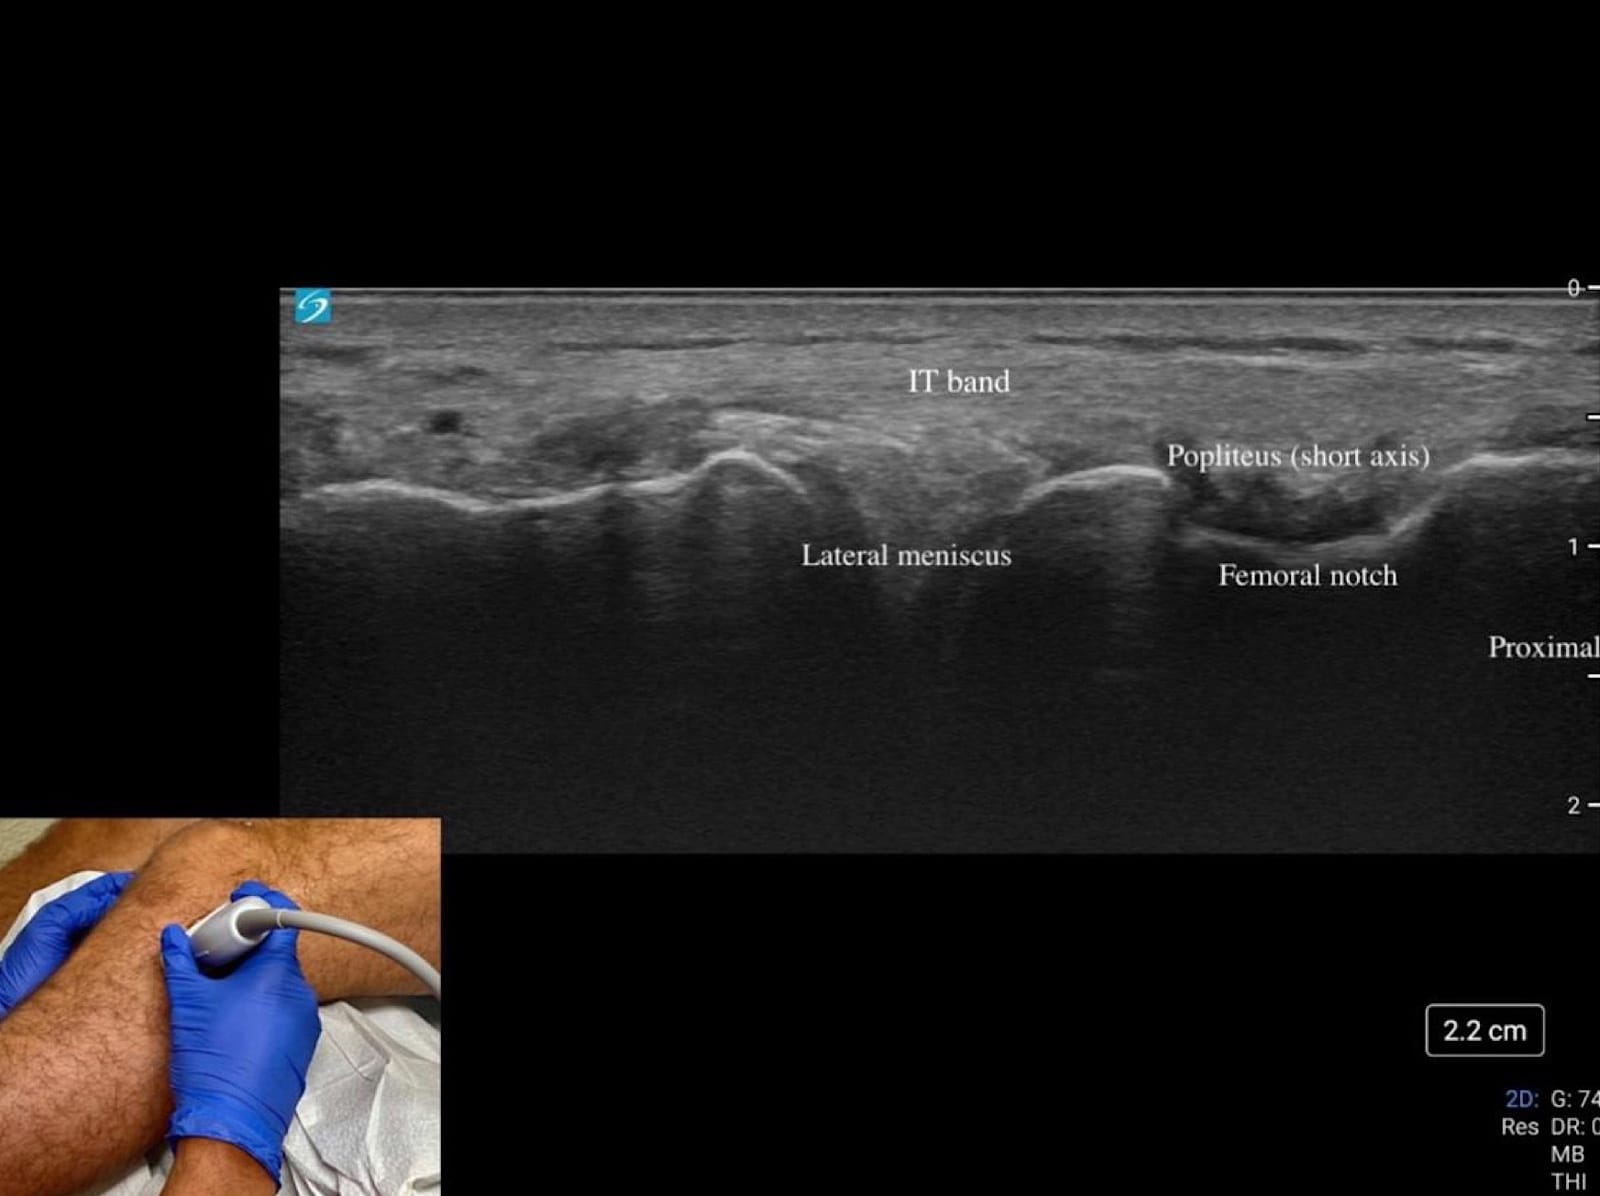

Start at “home base” by palpating Gerdy’s tubercle on the lateral tibia and the lateral femoral condyle, then place the transducer between these landmarks to identify the IT band as it courses superficially toward its distal insertion at Gerdy’s tubercle (refer to figure 7 and figure 3).

Trace the IT band proximally in long axis over the lateral femoral condyle, then rotate into short axis to scan anteriorly and posteriorly, with attention to focal thickening or fluid collection. Returning to the joint line, visualize the lateral femoral condyle superiorly and tibial plateau inferiorly as landmarks, then sweep anteriorly and posteriorly to evaluate the lateral meniscus for extrusion, clefts, or parameniscal cysts (refer to figure 7).

Translate posteriorly while tilting the transducer anteriorly to optimize the visibility of the meniscus body. This action will also reveal the popliteus tendon within the femoral notch, seen as a small hyperechoic structure in the short axis. Finally, assess the LCL as a thin echogenic band extending from the lateral femoral epicondyle to the fibular head, applying varus stress to evaluate its integrity dynamically.

Key Structures: Lateral collateral ligament (LCL), iliotibial band, lateral meniscus (Figure 7 and Figure 8A).